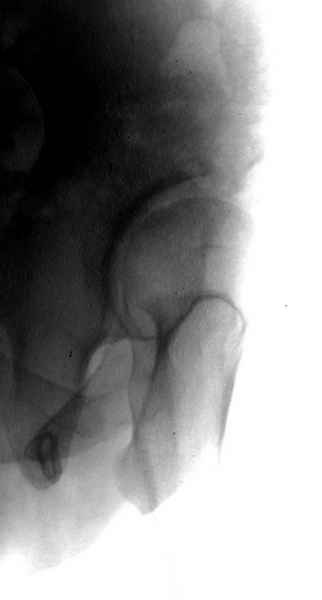

Картина типичной эволюции дисплазии сустава "кистовидная перестройка", на фоне неправильного взаймоотношения сустава "да тут угол Виберга 0 градусов" на вершине наибольшей нагрузки в вертлужной впадине образовался участок разрежения, "киста", в последующем через этот участок образуется перелом - стадия фрагментация дисплазии.

Для установки диагноза достаточно информации, на рентгенограмме передний и задний край ацетабулум образовали перекрест, "цифру восемь", указывающий на небольшую ретроверсию, а суставная щель одинаковой ширины на всем протяжении, что доказывает, что с покрытием хряща проблем нет. Головка бедра покрыта всего наполовину, это явное нарушения взаимоотношений.

А для данного случая, необходим прямой снимок таза с отдельными суставами, также включить боковые снимки сустава, немаловажно знание покрытия головки спереди.